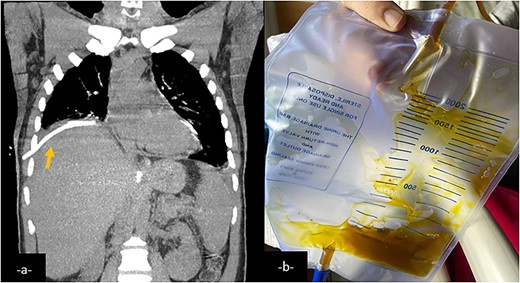

Coronal CT-scan reconstruction after an external drainage of the right pulmonary collection showing a decrease in size of it (a). External drainage finds a brownish fluid consistent with bile (b).